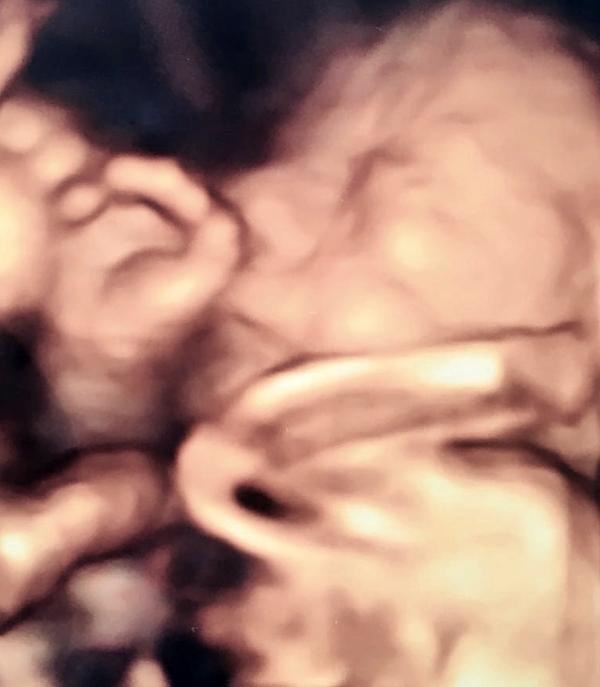

Anne karnındaki bebeklerin gülümseten pozları

Takip ettiği bebeklerin ilginç görüntülerini odasındaki panoya astığını söyleyen Op. Dr. Aksu, "Bebeklerin de mahremiyeti var. Eğer onlar kendilerini göstermek istemezse ben de geri çekilirim. zorlamam" dedi.